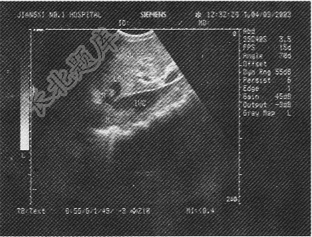

- 单项选择题某患者超声检查见肝脏及下腔静脉肝段内异常回声。超声表现如图,诊断考虑为

A、艾森门格综合征

B、布-加综合征

C、麦格综合征

D、Mirizzi综合征

E、马方综合征